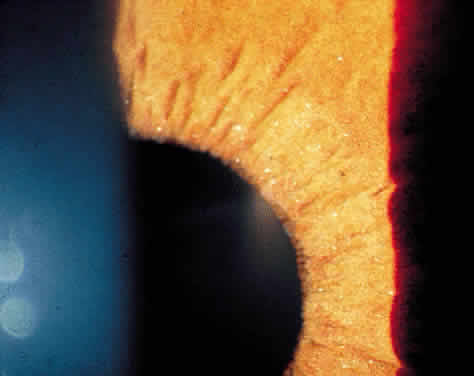

The iris often becomes atrophic in patients with chronic iridocyclitis. Atrophy of the posterior pigmented epithelium of the iris is more common in herpetic uveitis and may result in iris transillumination defects (Fig. 10). Anterior stromal atrophy is more characteristic of Fuchs' iridocyclitis and often results in heterochromia. The irides should therefore be examined by external inspection with the room lights on to document any heterochromia and at the slit lamp to document transillumination defects.

Fig. 10. Extensive iris transillumination defects in a patient with herpes simplex iridocyclitis.